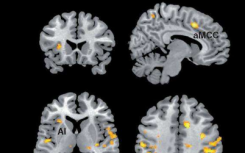

压力可以增强同理心

急性社会心理压力会导致同理心和亲社会行为的增加。由维也纳大学克劳斯·拉姆领导的国际研究小组研究了压力对神经机制的影响,并在一项...